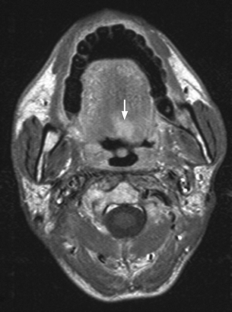

The aim of this study was to document the sites and MRI features of radiation-induced tumors (RITs) in the head and neck following treatment for nasopharyngeal carcinoma (NPC). The MRI examinations and clinical records of 20 patients with 21 RITs were reviewed retrospectively. RITs developed 3–30 years after radiotherapy and included eleven squamous cell carcinomas, six sarcomas, two neuroendocrine carcinomas, one mucoepidermoid carcinoma and one meningioma. RITs arose in the maxillary region (9), oro/hypopharynx and oral cavity (5), external auditory canal (4), nasopharynx and sphenoid sinus (2) and brain (1). Radiation-induced carcinoma and sarcoma had MRI features that were useful to distinguish them from recurrent NPC. To improve early detection of RITs, the check areas on an MRI of a patient with previous NPC treated by radiation should always include the maxillary region, tongue, and external auditory canal/temporal bone.

Fig. 1